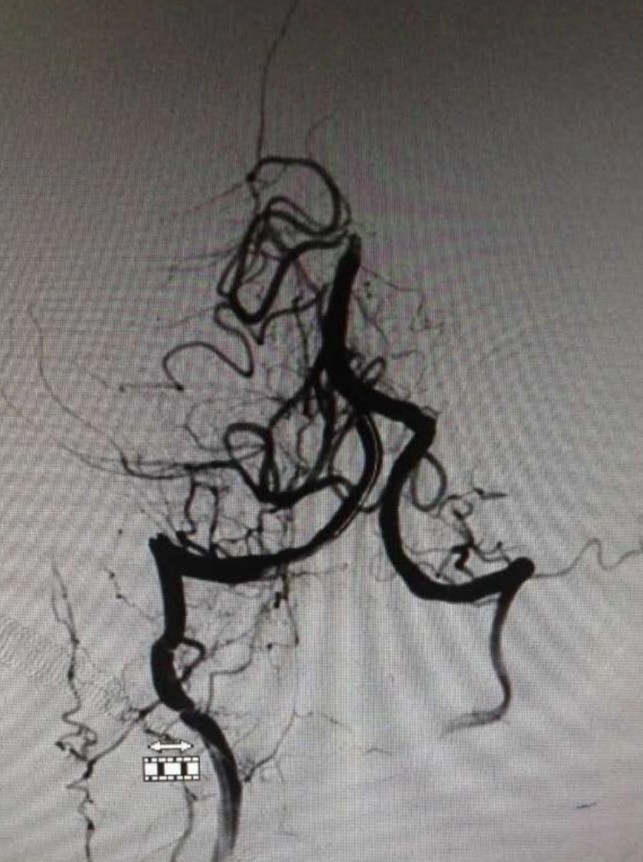

▼右椎动脉造影见基底动脉末端闭塞。双侧颈内动脉造影无殊,双侧后交通未见显影。

通过造影明确病变为基底动脉末端闭塞,机制?

1:左椎动脉急性闭塞同时血栓脱落远端栓塞?

2:左椎动脉是陈旧性闭塞,闭塞末端血栓脱落或者基底动脉原位血栓?

问题焦点是左椎动脉是否是急性闭塞,这直接决定开通策略不同:如果是急性闭塞那么先开通左椎再开通基底,如果不是那么就直接开通基底。根据片子很难准确判断左椎是否是急性闭塞,纠结后决定直接去开通基底:椎动脉长段闭塞而且肌支代偿很好,应该是陈旧性闭塞可能大,尽快开通基底为患者争夺时间。